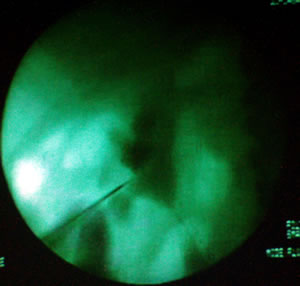

Профессор предпочитает проводить пункцию под контролем

рентгена, а не под контролем УЗИ, считает, что это позволяет

иметь стереоскопическую картину.

Алексей Георгиевич начал операцию с пункции лоханки через

нижнюю чашечку пункционной иглой под контролем рентгена.

Лоханка при проведении пункции контрастирована по меточнику.